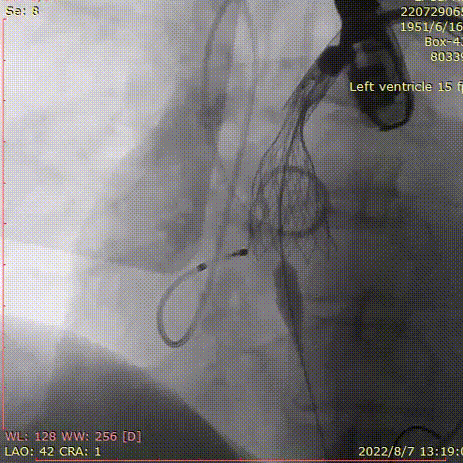

手术过程

20mm球囊预扩张:

球囊有明显腰征,无漏。

术后造影:

大鞘撤出外周血管,造影

术中20mm球囊预扩可见明显腰征,无瓣周漏,左冠充盈速度可。选择TaurusElite  AV23瓣膜送至主动脉弓,输送系统轻松过弓及跨瓣,精准定位无冠窦最低点,利用可回收功能,术中对位置进行适当调整,大大提升了瓣膜精准释放的几率,保证了手术的安全性。